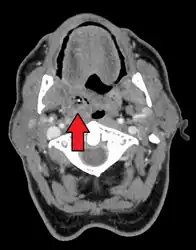

Diagnosis is usually based on the symptoms.[1] Medical imaging may be done to rule out complications.[1] Medical imaging may include CT scan, MRI, or ultrasound is also useful in diagnosis.[1]

-

Peritonsillar abscess on the person's right as seen on CT imaging -

Peritonsillar abscess